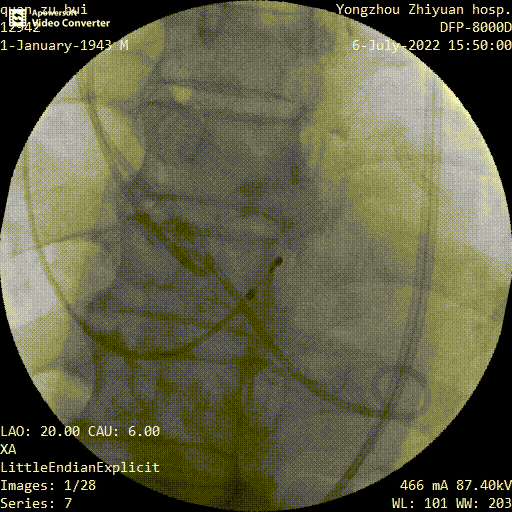

主动脉根部造影

球囊预扩

瓣膜定位

释放到工作位

多角度观察

最终释放

手术过程中,在完成跨瓣操作后,23mm球囊预扩有轻微腰征、无造影剂渗漏,预装TaurusElite AV29瓣膜到位,输送系统快速、顺利地完成过弓、跨瓣操作,于瓣环上约2mm定位释放;针对本例患者瓣叶明显增厚伴重度钙化,左右窦间可见钙化融合嵴的特点,TaurusElite瓣膜高密度流入端设计提供了足够的径向支撑力,保证了瓣膜的锚定力,瓣膜内外双裙边设计能提供良好的辅助锚定力,有效减少瓣周漏。此外,本例患者左窦间存在长条状钙化延伸至瓣环下10mm水平,释放位置偏深可能存在起搏器植入风险,TaurusElite瓣膜具有多次完全可回收,回收后可重新跨瓣、释放的特点,给予术者足够的信心完成高位释放的操作,释放后最终瓣架底端位于瓣环下约1mm,实现了释放位置的精准控制,有效的减少了起搏器植入风险,确保了手术安全、顺利的完成。这例手术为永州地区开展的第一台TAVR手术,填补了该地区TAVR技术空白,标志着永州市心脏瓣膜疾病诊治迈入了全新的微创治疗时代!